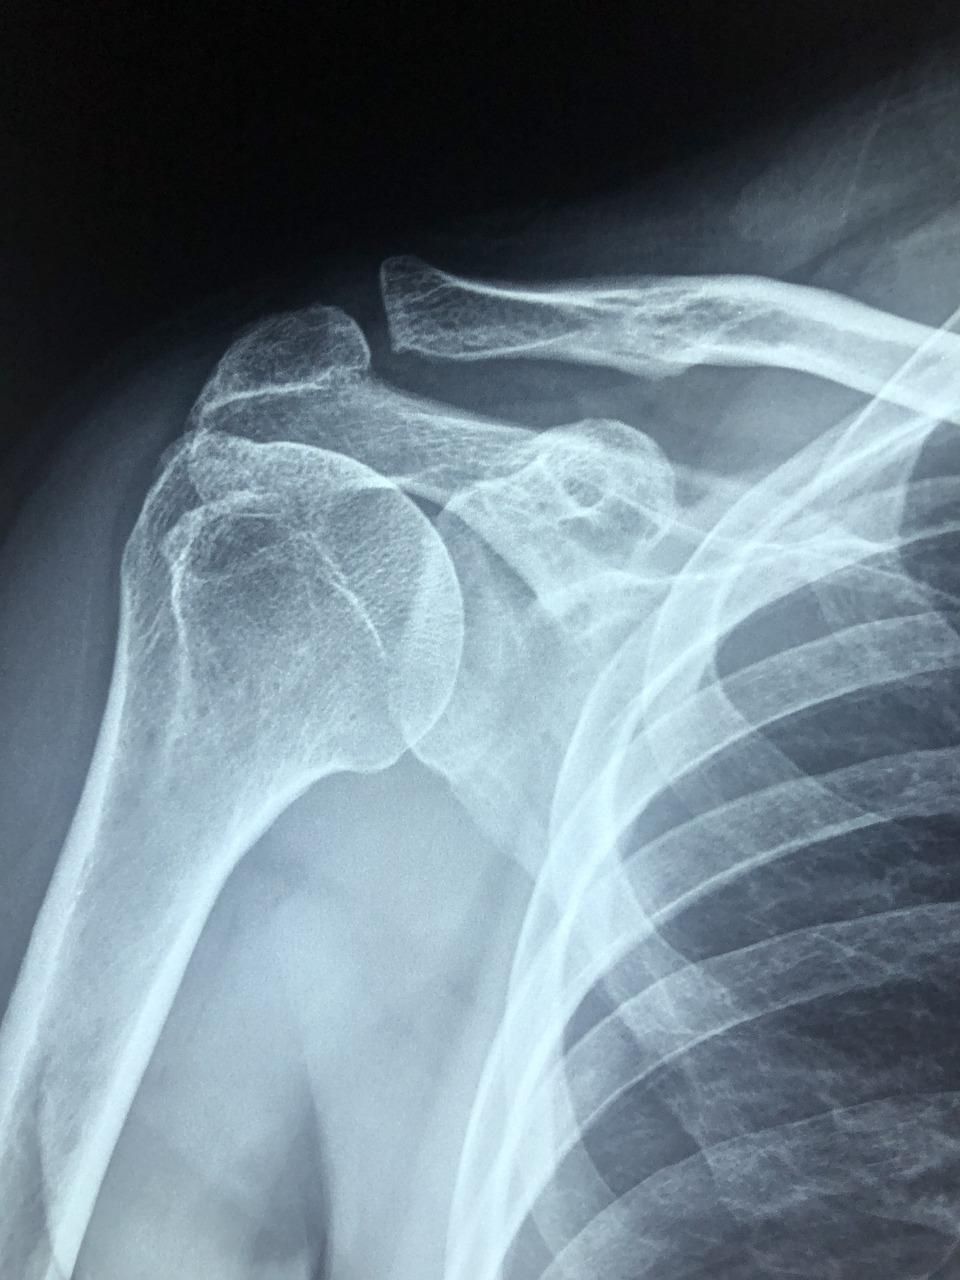

Plasma rico en plaquetas en hombro en Madrid Centro para cambiar tu vida

El Dr. López Velázquez es un médico experto y con amplia experiencia en la infiltración ecoguiada de plasma rico en plaquetas (PRP) en hombro en Madrid Centro.

Se trata de un tratamiento natural y biológico con potente acción antiinflamatoria y regeneradora. Muy beneficioso en bursitis, tendinitis y roturas parciales de tendones del hombro.

▪ Realiza la infiltración de plasma rico en plaquetas con guía de imagen ecográfica (infiltración ecoguiada). Guía la aguja hasta la localización exacta de la lesión del tendón, consiguiendo así la máxima precisión. Es más, puede visualizar en la pantalla del ecógrafo cómo el plasma está siendo inyectado. Es la garantía de máxima eficacia.